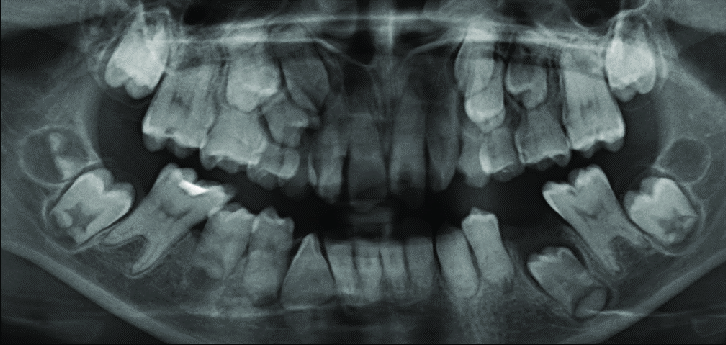

8 / 30

8. (Select ONE OR MORE correct answers)

Tooth 8.4 shows evidence of